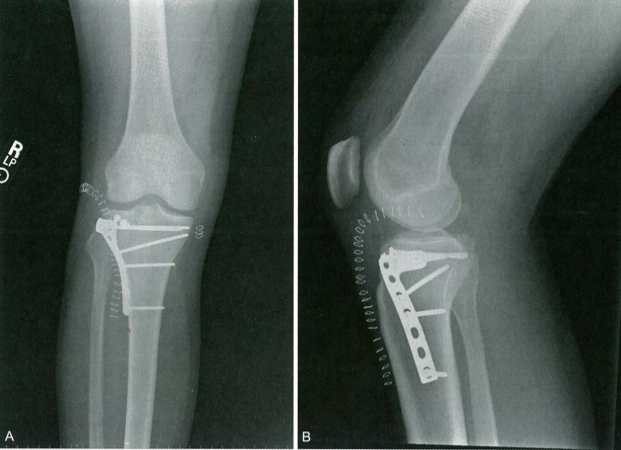

Тип II – тотальный перелом мыщелка:

Этот тип перелома-вывиха может затрагивать медиальное или латеральное плато большеберцовой кости, а линия перелома проходит ниже межмыщелковой ости до контралатерального отдела сустава, что отличается от переломов IV типа (рис. 3). Среди них 50% переломов связаны с повреждением контрлатеральной коллатеральной связки, что приводит к перелому или вывиху проксимального отдела малоберцовой кости. На этот тип приходится 25% всех переломов и вывихов, 12% из которых сопровождаются повреждением сосудов и нервов. Чтобы определить, существует ли потенциальное повреждение связок, необходимо провести стресс-тестирование. Стабильные переломы можно лечить с помощью гипсовых брекетов, тщательного наблюдения и отсроченной нагрузки. При нестабильных или плохо репонируемых переломах после закрытой или открытой репозиции можно выполнить межфрагментарную винтовую фиксацию, восстановление поврежденной связки, фиксацию трубчатыми скобками и отсроченную нагрузку на ногу.

Рисунок 3. Перелом и вывих плато большеберцовой кости. A. Перелом и вывих плато большеберцовой кости II типа, фиксируемый стальной пластиной и винтами. B. Внутренняя фиксация поддерживающей пластиной и винтами. Классификация Шацкера является одним из наиболее широко используемых методов классификации в клинической работе. Исследования Рао Хайцзюня и др. показали, что послеоперационные осложнения у пациентов с переломами плато большеберцовой кости различных классификаций Шацкера в основном связаны с недостаточной оценкой степени измельчения, местоположения и направления перелома, что приводит к неправильному хирургическому подходу и фактическому выбору метода. что увеличивает редукцию переломов и инфицирование, некроз кожи и другие осложнения, очевидной связи с классификацией Шацкера нет, что согласуется с результатами этого исследования. Переломы плато большеберцовой кости обычно возникают в результате высокоэнергетических травм. Пациенты часто страдают от повреждения тканей. Область вокруг коленного сустава представляет собой область со слабым кровоснабжением и покрытием мягких тканей. Суставы и сухожилия покрывают только подкожная клетчатка и кожа. Неправильное время Операция может вызвать у пациентов сильный отек, который может привести к некрозу связок и сухожилий, кожной инфекции и некрозу.